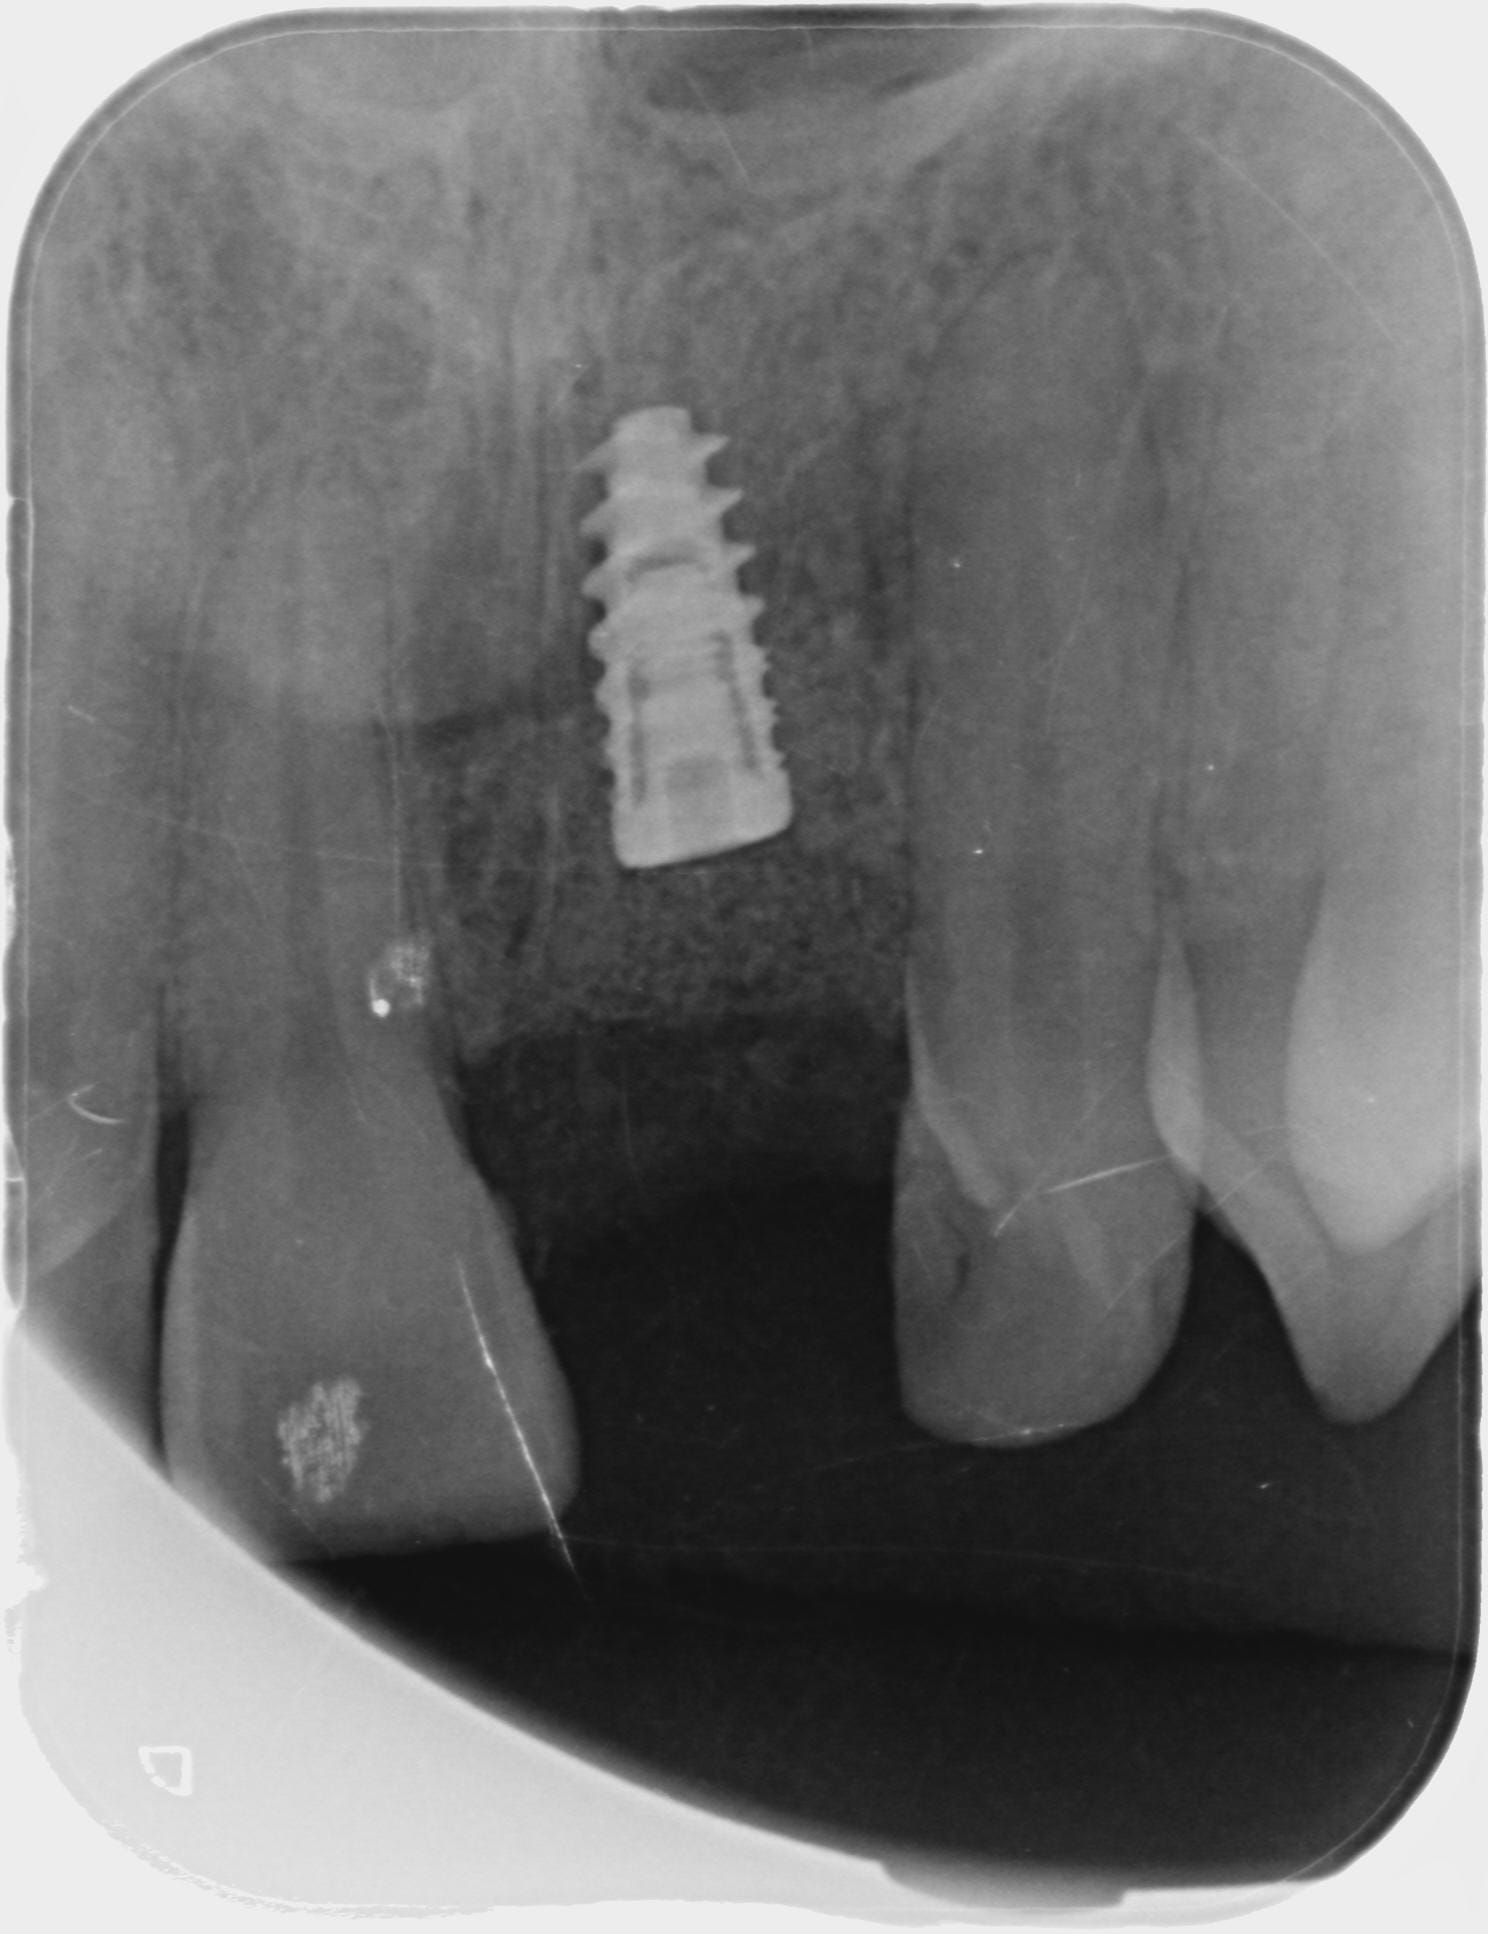

Exo de la 21 début janvier de cette année, et la semaine dernière pose d'un implant GlobalD InKone 3.5 L8.5, pose à 50-55 N.cm

Quelques images du cone beam et de la planif

Planif 1 owxhvi - Eugenol

Planif 2 slmeas - Eugenol

Planif 3 v71j9j - Eugenol

Planif 4 my2dza - Eugenol

Planif 5 fqtf2p - Eugenol

Planif 6 ody3rj - Eugenol

Pourquoi l'avoir enfoui autant? tu penses pas que tu va galérer pour la partie prothétique?

L'InKone est prévu pour être placé en sous crestal de 2mm normalement.

Euh... ton implant est très très enfoui esthétiquement je pense que ça va pas être une super surprise (même si elle recouvre, pense que les patients regardent toujours en soulevant la lèvre...) ensuite par rapport à l'apex de ta 11 il semble très haut, je ferai une 3D perso pour voir mon plancher des fosses nasales.